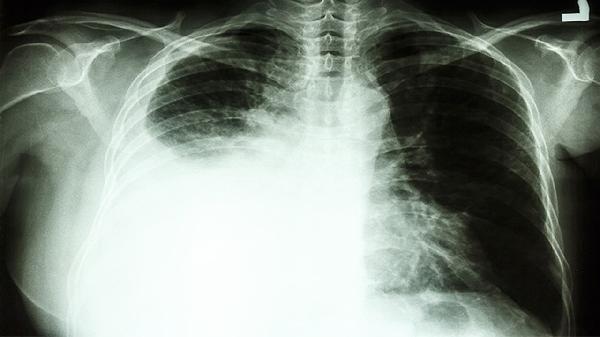

重度肺高压虽然无法彻底治愈,但通过合理的治疗和生活方式的调整,症状可以得到有效缓解,并有可能延长寿命。重度肺高压通常是由于长期的肺部疾病或先天性心脏病导致的肺血管阻力增高引起的。虽然这种情况不能完全根治,但通过积极的干预措施,可以减轻症状,提高生活质量,并减少并发症的发生,从而延长生命。

1、治疗原发病因:重度肺高压的治疗首先要针对其原发病因进行。比如,如果是由于慢性阻塞性肺疾病(COPD)引起的,就需要积极治疗COPD。通过药物、氧疗等手段来降低肺动脉压力是常见的做法。

4、定期检查:定期复查肺功能、心脏超声等检查项目是必要的。这有助于医生及时发现病情变化,并调整治疗方案。患者在日常生活中也要密切关注自己的身体状况,尤其是在急性发作期,需密切监测心肺功能,以避免进一步恶化。